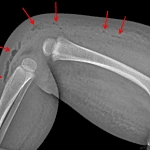

- Extensive fat stranding and edema involving the right hip, thigh, and knee with locules of gas tracking along deep fascial planes from the anterolateral knee proximally to the mid thigh

- Necrotizing fasciitis

Extensive fat stranding and edema involving the right hip, thigh, and knee with locules of gas tracking along deep fascial planes from the anterolateral knee proximally to the mid thigh. Findings are concerning for cellulitis and possible necrotizing fasciitis. Recommend surgical consultation.

Limited evaluation of the right knee with effusion/septic arthritis not excluded.

No acute fracture or malalignment.